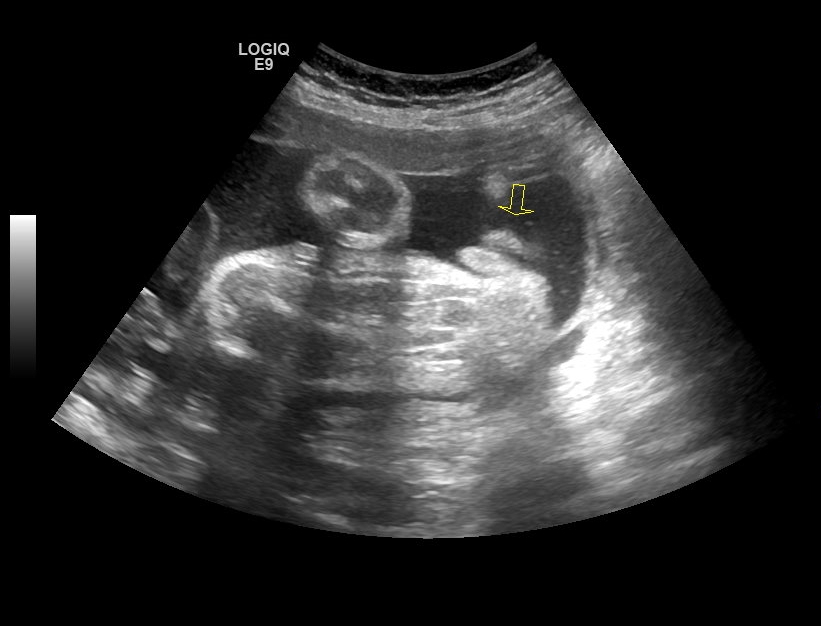

18 week Gender Scan, UPDATE!! from previous post 12 week 4 days scan :)